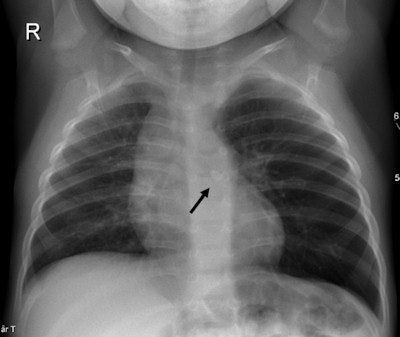

Viral infections are more frequent than bacterial infections in infants and may cause pneumonia. Bacterial infections are more commonly diagnosed in children age 5 and older. Chest x-ray exams are the exam of choice, although approximately 30% of children with viral infections have normal chest radiographs.

Pleural empyema is increasingly being seen, both as a result of improved diagnosis and the reduced number of patients treated with antibiotics, according to de Lange. Chest radiographs and ultrasound exams should be the first exams ordered.

A CT scan should be ordered only when ultrasound and chest x-ray exams do not distinguish a loculated empyema from an intraparenchymal abscess or a cavitary necrosis/necrotizing pneumonia. Contrast-enhanced CT exams may be required to identify the position of drains, loculations, and parenchymal complications in patients who do not respond to treatment. Exposure to the CT radiation dose may also be warranted when imaging suppurative lung parenchymal complications because of CT's sensitivity and ability to detect and establish the extent of the complication.